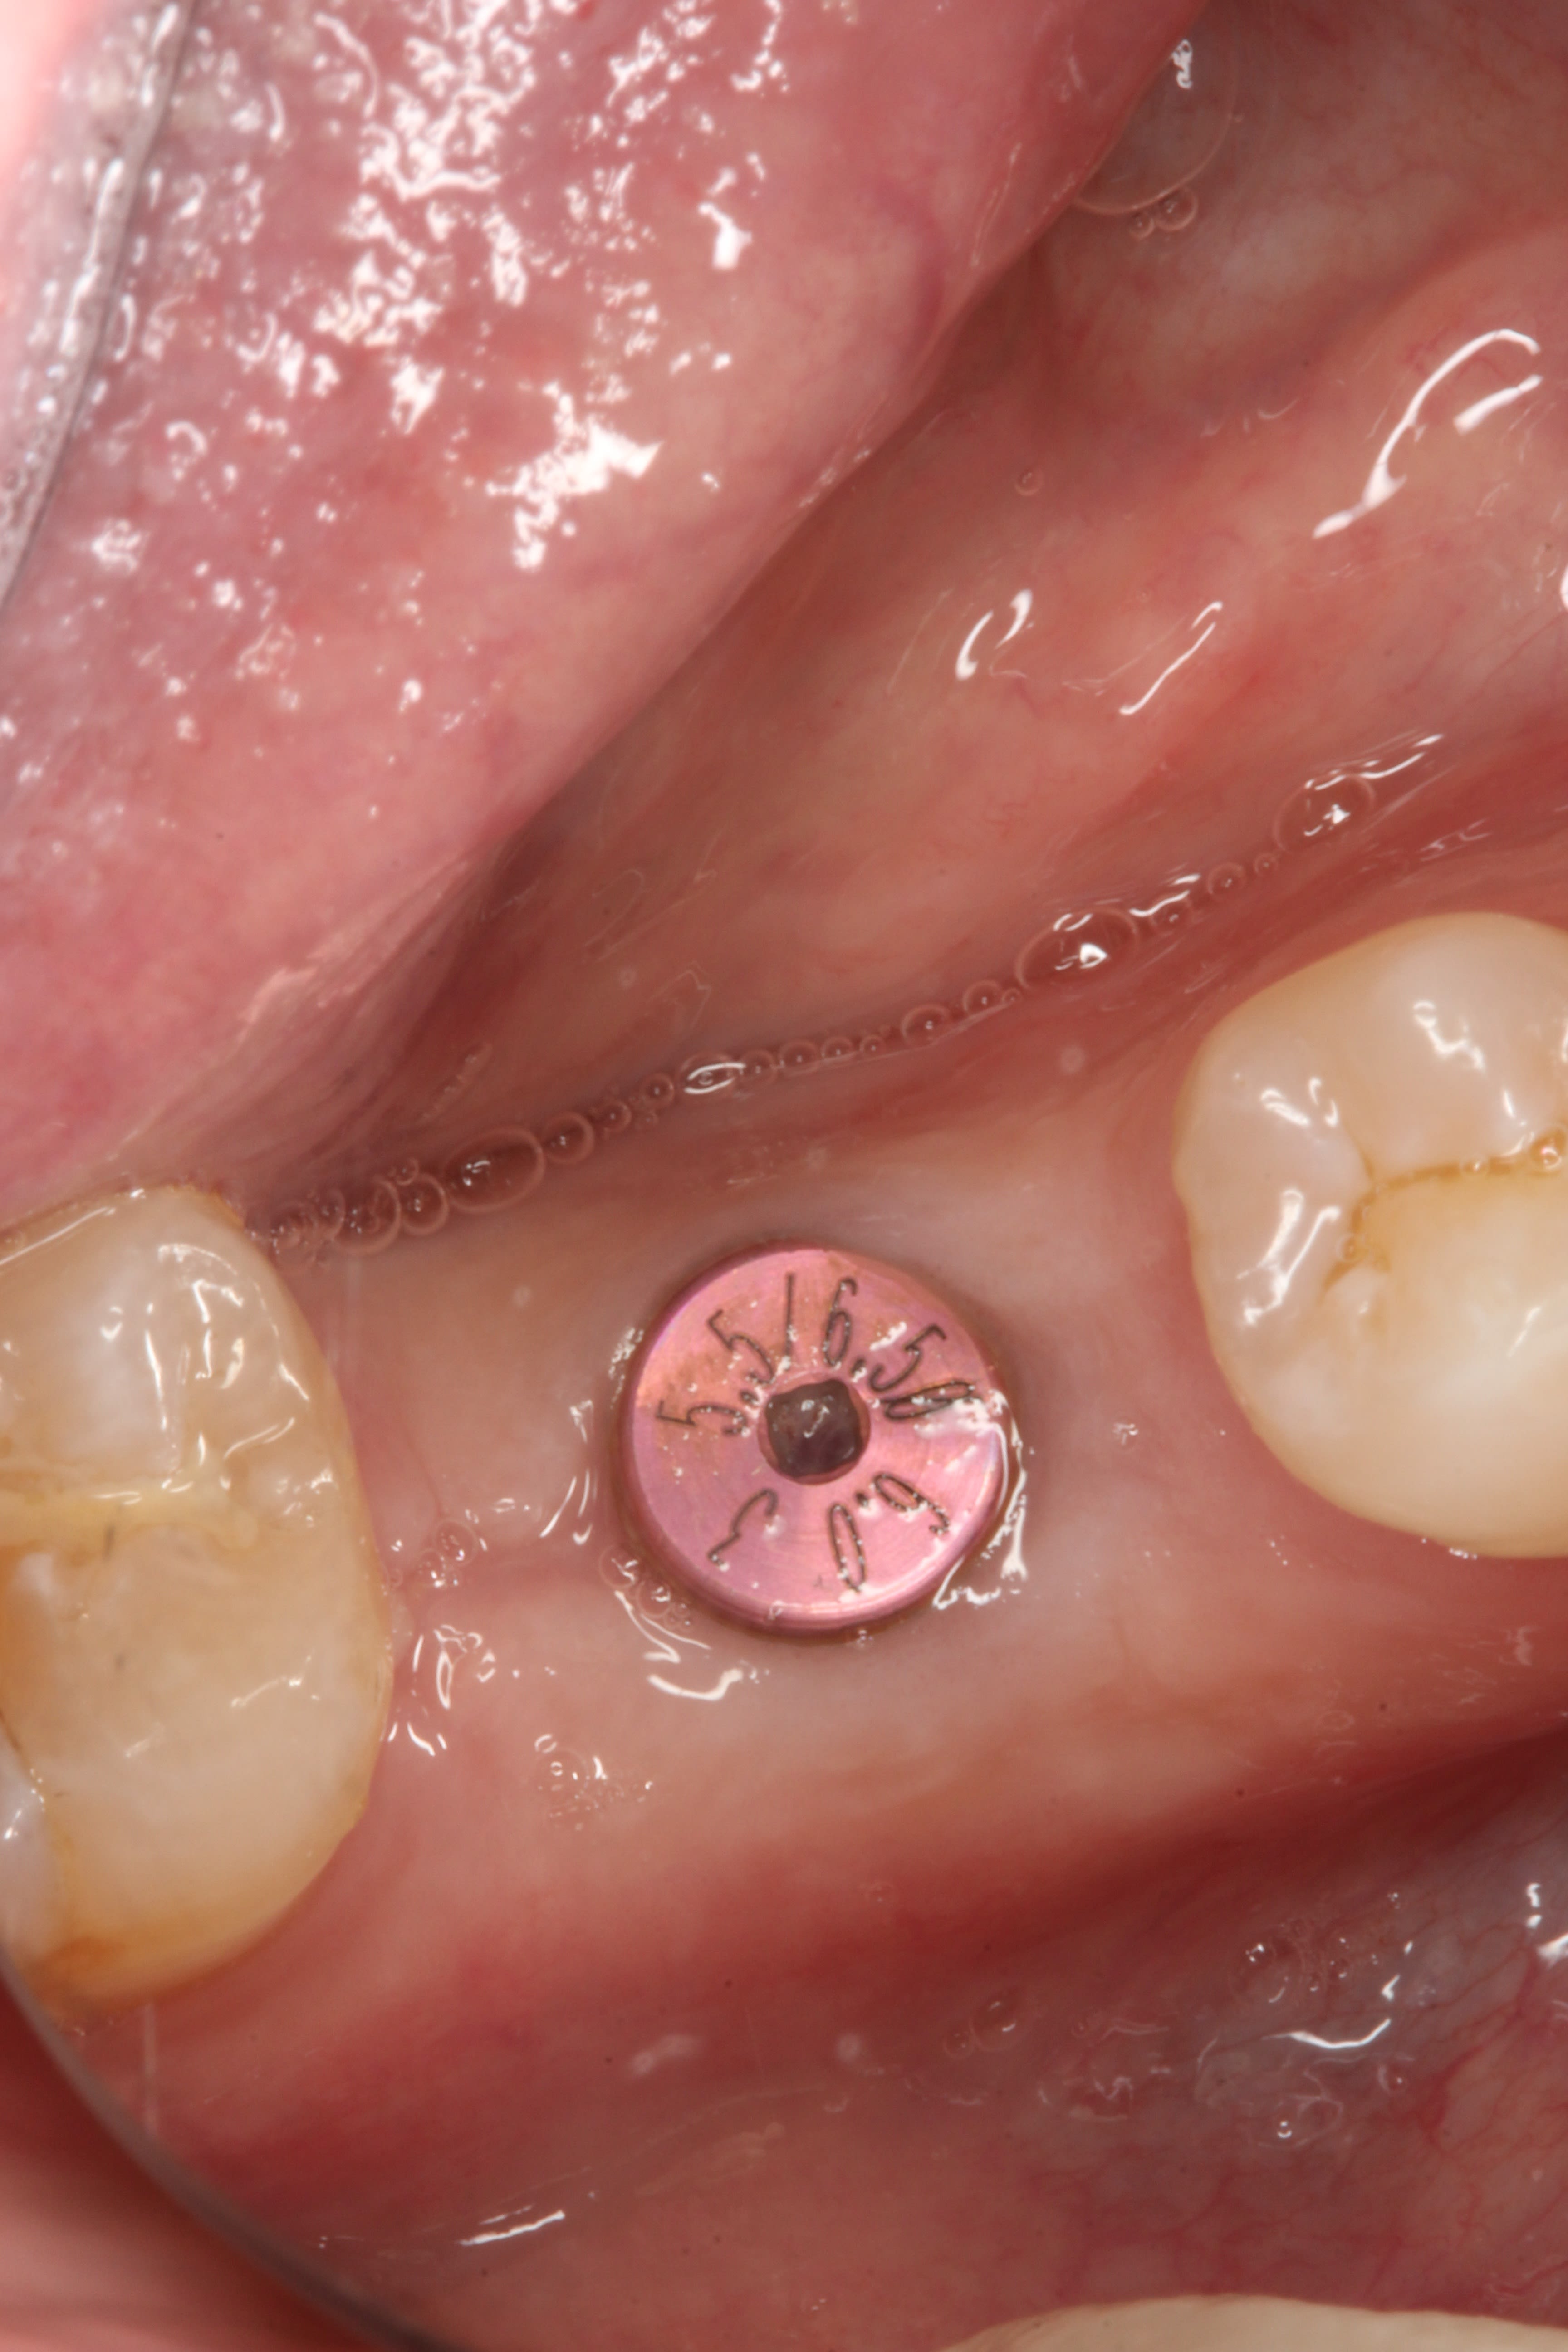

In February 2012 the patient enrolled in the multicenter study, and a 5.5-mm x 11.5-mm implant (Genesis) was placed (Figure 42). Minor contour bone grafting of the site was also performed using autogenous bone directly against the buccal cortex and layered thereafter with a corticocancellous allograft (Puros) along the lateral aspect of the implant. This was done to increase the peri-implant bone and mucosal thickness (existing bone thickness was <1 mm on the buccal aspect) in an effort to improve parameters that would reduce the incidence of recession over the long term.

The 5.5-mm implant platform was used to accommodate the high occlusal load typically associated with the molar area and to optimize the esthetic emergence profile of the final restoration, neither of which would have been feasible with a narrower implant, even in the presence of more robust socket augmentation. A healing abutment was placed (Figure 43).